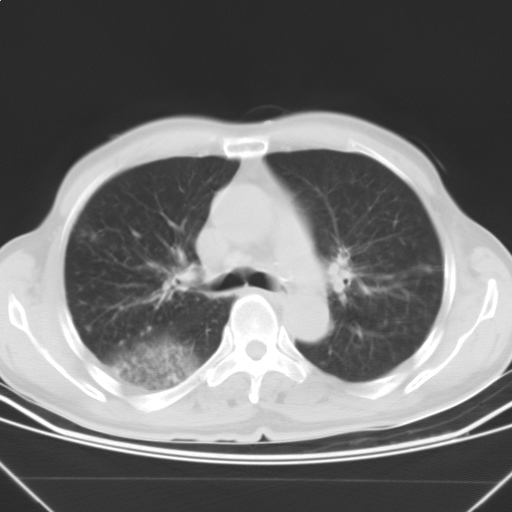

以下是引用随光逐影在2009-5-1 13:53:00的发言:[br]考虑为:1)两肺血行播散型肺结核;2)右肺下叶炎症感染。3)右侧胸膜增厚。